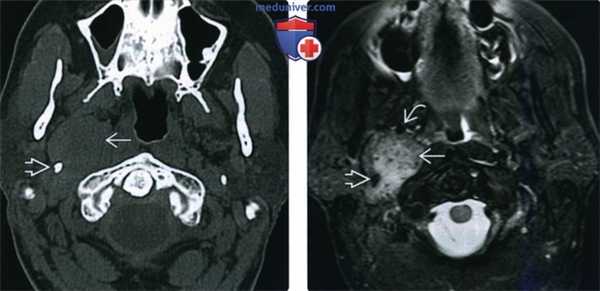

(Слева) КТ без КУ, изоденсная опухоль, расположенная в правом сонном пространстве. Шиловидный отросток смещен в латеральную сторону. И хотя шиловидный отросток чаще располагается кпереди от сонного пространства, вагальные параганглиомы обычно смещают его в латеральную сторону, а не вперед.

(Справа) МРТ Т2ВИ STIR, этот же пациент. Сигнал от опухоли умеренно гиперинтенсивный. Внутренняя сонная артерия смещена вперед и в медиальную сторону, шиловидный отросток смещен в латеральном направлении.